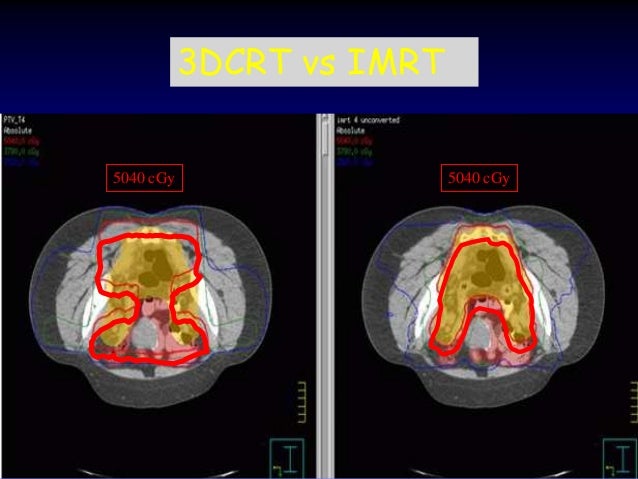

60. 60. 3DCRT vs IMRT 5040 cGy 5040 cGy